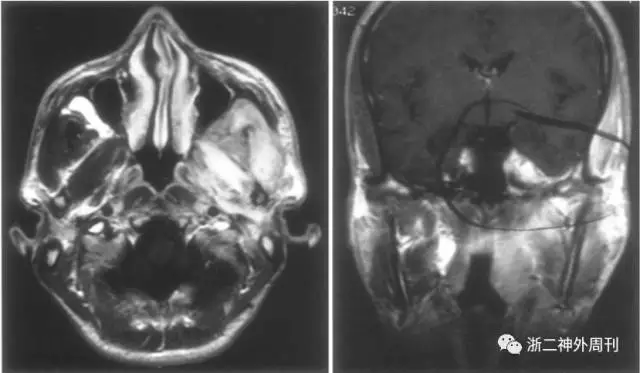

韧带样纤维瘤质硬,多见于腹壁,也可发生于腹内及骨骼肌内。颅内罕见,发生在颅底的仅见个例报道[8,9](图7和图8)。

图8. 韧带样纤维瘤MRI表现:位于左侧颞下窝的增强明显的肿物,呈浸润性生长,侵犯Meckel腔、Dorello管和海绵窦。